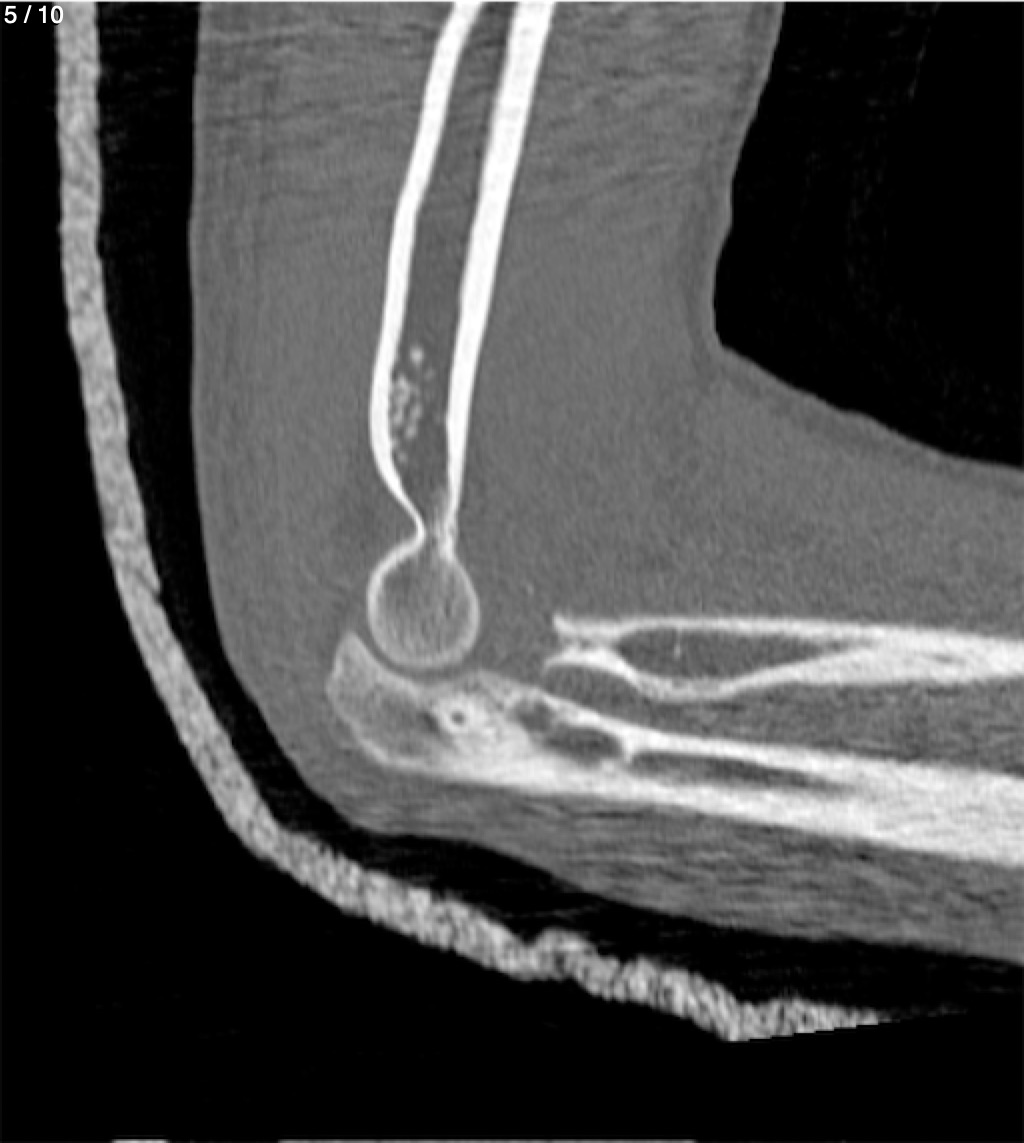

Antonio Dominguez Tino 21 A - Tac Codo Izq